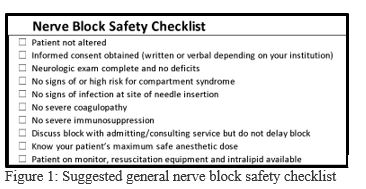

1. Use a safety checklist (Figure 1)

With any nerve block we recommend using a safety checklist.